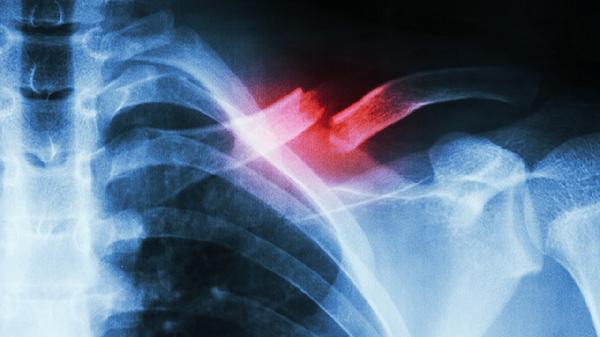

胸肋骨骨折嚴(yán)重嗎?

關(guān)鍵詞: #骨折 #肋骨 #肋骨骨折

肋骨骨折是否嚴(yán)重需根據(jù)骨折程度判斷,輕微骨折通常不嚴(yán)重,嚴(yán)重骨折可能危及生命。

肋骨骨折若僅出現(xiàn)單根肋骨裂紋或輕微移位,通常不會(huì)對(duì)呼吸功能造成明顯影響。這類骨折多由直接外力撞擊或跌倒引起,表現(xiàn)為局部壓痛和深呼吸時(shí)疼痛加劇?;颊呖赏ㄟ^胸帶固定、口服布洛芬緩釋膠囊或?qū)σ阴0被悠徑馓弁矗浜吓P床休息2-4周可逐漸恢復(fù)。此階段需避免劇烈咳嗽和胸部擠壓,防止骨折端二次移位。

多根肋骨骨折伴明顯移位或連枷胸屬于危急情況。骨折斷端可能刺破胸膜導(dǎo)致氣胸,損傷肋間血管引發(fā)血胸,或刺傷肺組織造成血?dú)庑?。這類損傷常伴隨呼吸困難、皮下氣腫和反常呼吸運(yùn)動(dòng),需立即進(jìn)行胸腔閉式引流術(shù),必要時(shí)行肋骨內(nèi)固定術(shù)。嚴(yán)重并發(fā)癥可能引發(fā)呼吸衰竭或感染性休克,需在重癥監(jiān)護(hù)室進(jìn)行機(jī)械通氣和抗感染治療。